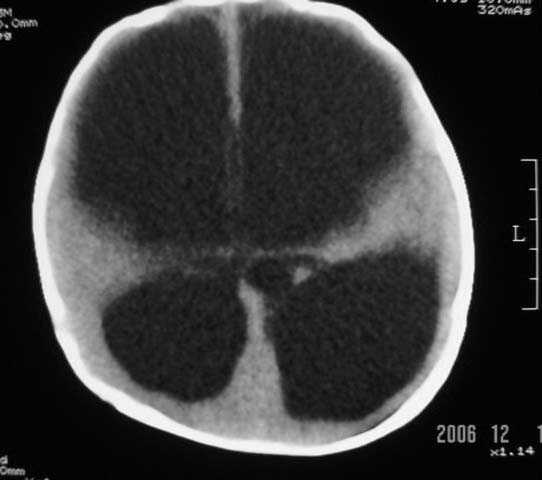

3m,出生时有新生儿吸入性肺炎、hie、化脓性脑膜炎,近一个月发现头围增大(51cm),无恶心呕吐。

第四脑室有增大,应该是交通性脑积水

3m,出生时有新生儿吸入性肺炎、hie、化脓性脑膜炎,近一个月发现头围增大(51cm),无恶心呕吐,脑室系统全程扩张,脑皮质变薄,结合病史考虑交通性脑积水

脑室全部扩大结合化脓性脑膜炎病史考虑重度交通性脑积水.

3m,出生时有新生儿吸入性肺炎、hie、化脓性脑膜炎,近一个月发现头围增大(51cm),无恶心呕吐,脑室系统全程扩张,脑皮质变薄,结合病史考虑重度交通性脑积水。